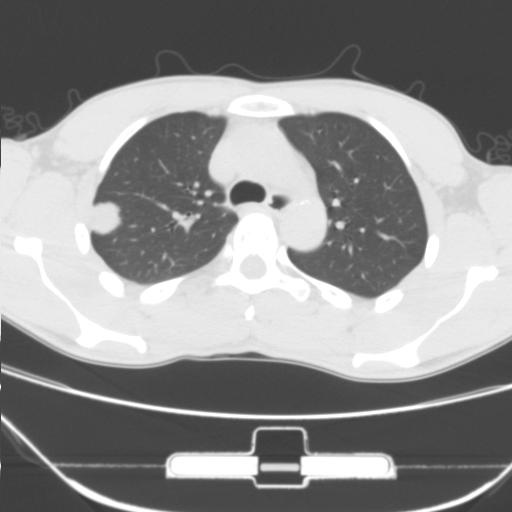

右肺上叶后段近胸膜下结节样异常密度灶,似见分页及毛刺,考虑右肺上叶周围型肺ca,建议穿刺病理检查

缺乏病史,症状体征,但这个孤立结节具备了几乎所有的恶性征象:分叶,毛刺,空泡征,胸膜凹陷征,血管集束。

考虑右肺上叶后段周围型肺癌。